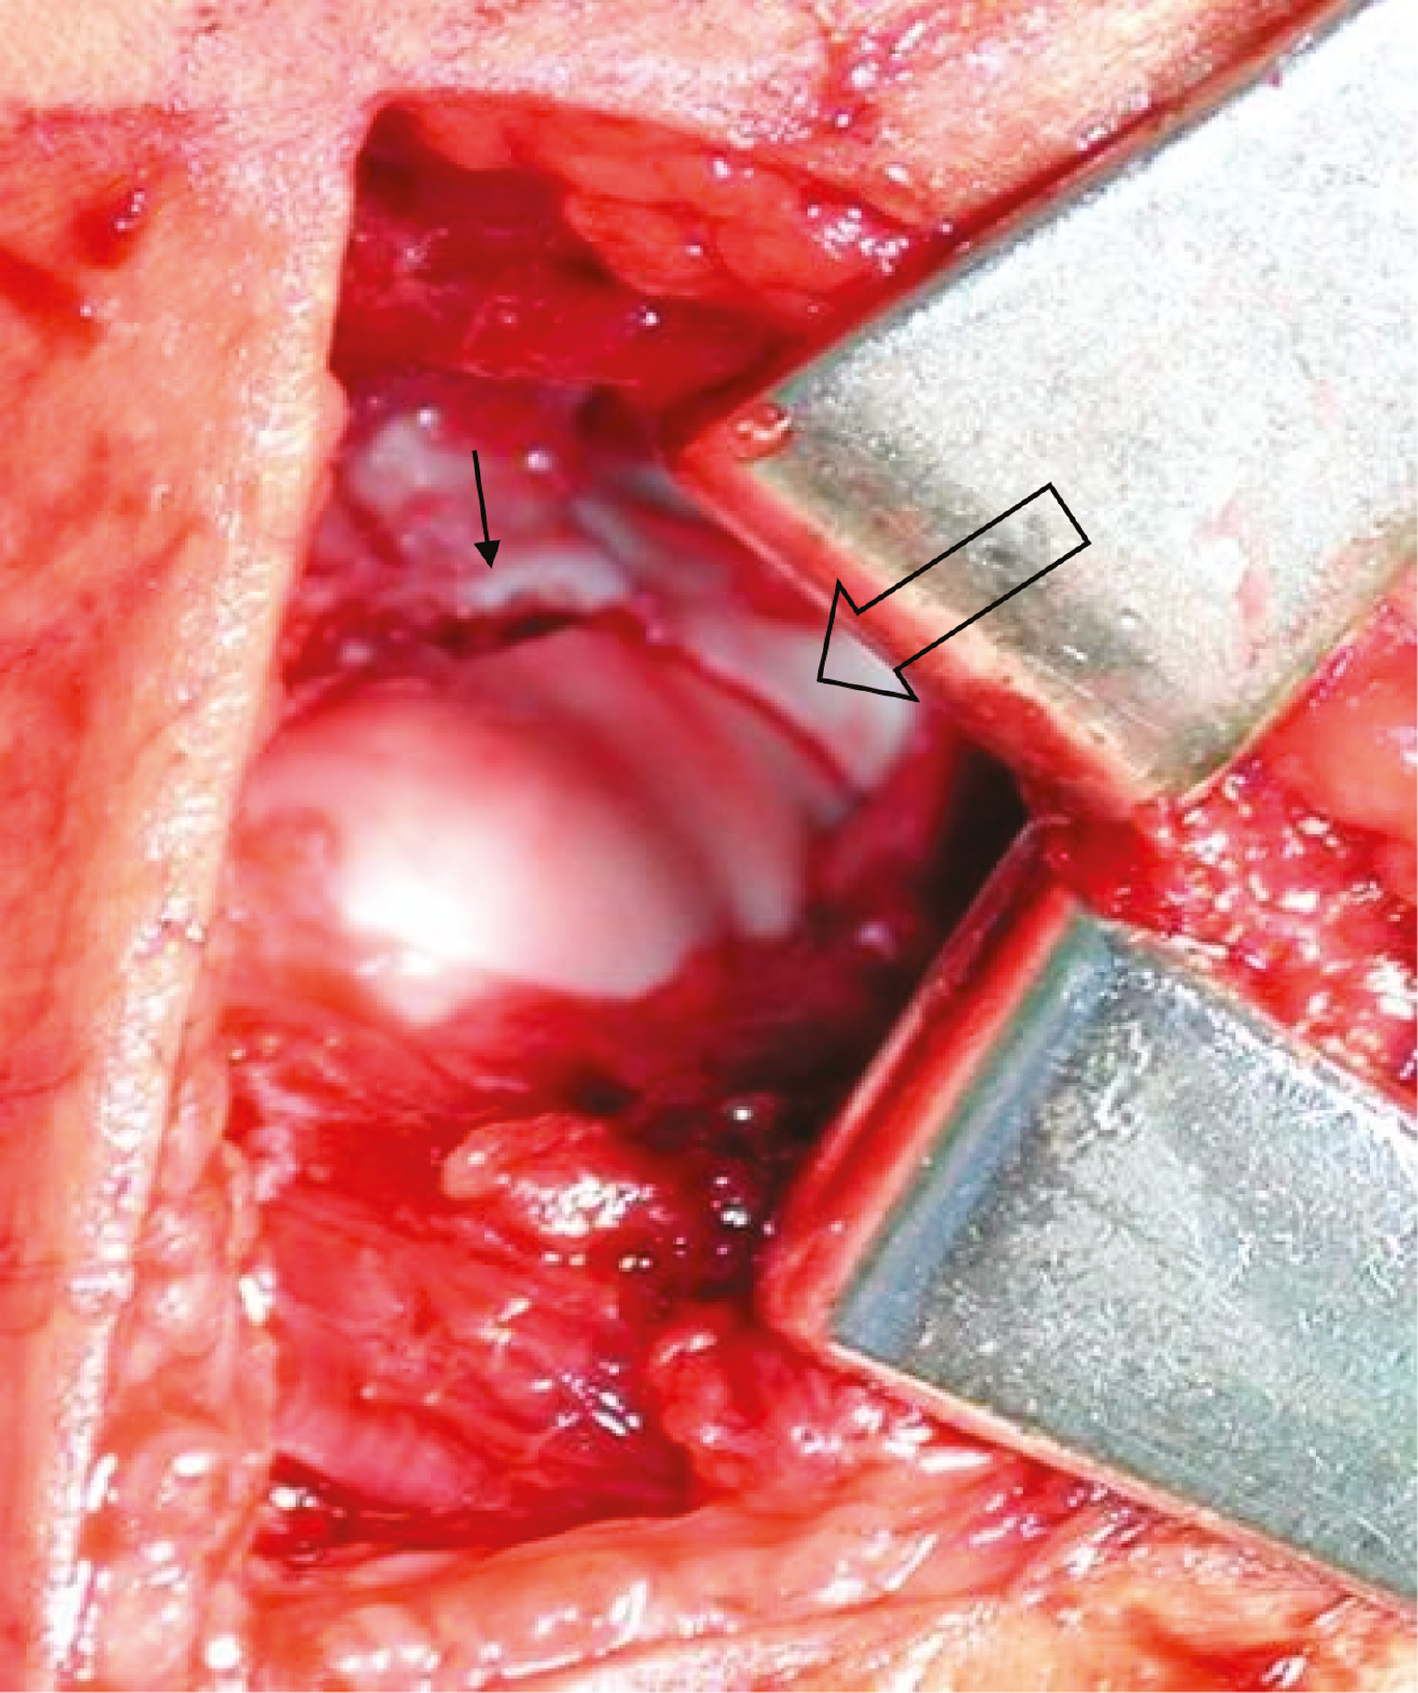

Success in this technically challenging procedure is best achieved with the use of an assistant—one surgeon holds reduction while another places the pins. Through direct visualization (Figure 15) and then palpation of the articular surface with a Freer elevator, the reduction is verified with fluoroscopic confirmation of reduction and proper pin placement. If there is concern about stability, a third pin can be placed in a divergent fashion. Good results have also been achieved utilizing a single 3.5/4.0 mm partially threaded, cannulated screw if greater stability is indicated. It should be oriented perpendicular to the fracture plane and often a second wire is placed to control rotation during drilling and screw insertion. This screw may become symptomatic in the future and necessitate elective removal.

Figure 15. Direct visualization of the articular surface of the distal humerus after closed reduction and pinning of the lateral condyle fracture. Notice the anatomic reduction of the articular surface (open arrow) with associated small amount of metaphyseal gapping superior to the articular surface (small arrow). Photo courtesy of Gregory Mencio, MD.